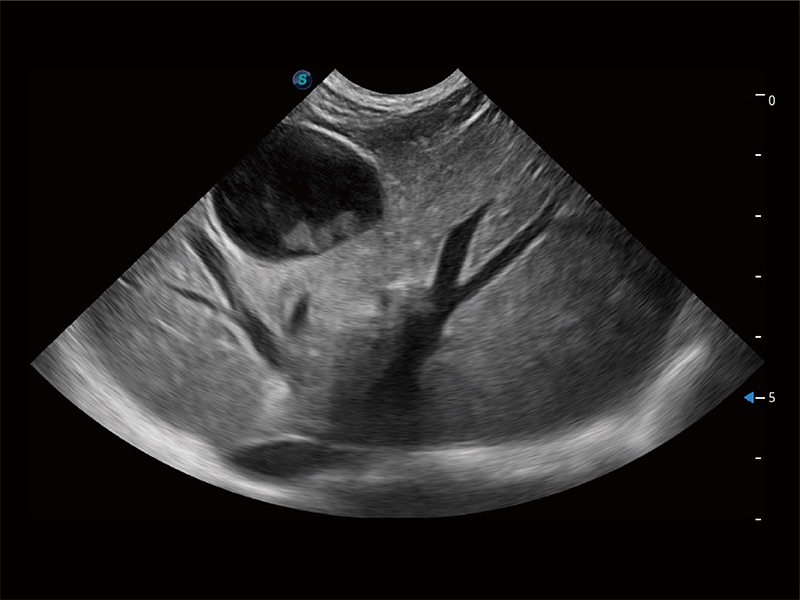

高性能和先进的临床应用工具可以为动物医生提供临床信心。ProPet 80 搭载了先进的腹部和浅表应用工具,帮助医生在日常临床实践中发挥前所未有的作用。

操作简便,无需高频度外力作用即可真实反映组织的形变,快速评估肿瘤良恶性。

非线性融合造影成像充分利用谐波和基波信号,为难以观察的血流进行增强显像。可用于线阵、凸阵、微凸阵、相控阵探头。